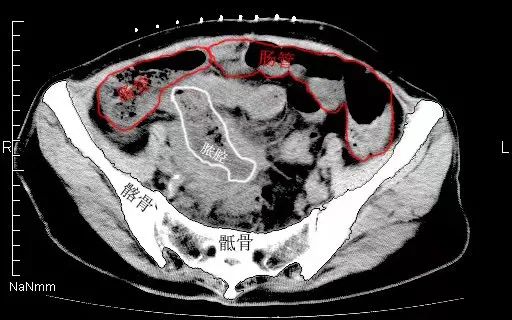

近日,患者王女士因阑尾炎术后一周,持续发热、腹痛难耐,来到徐州市中医院寻求进一步治疗。 中下腹扫描后,影像科严金明主任仔细阅片并了解相关病史后,考虑...